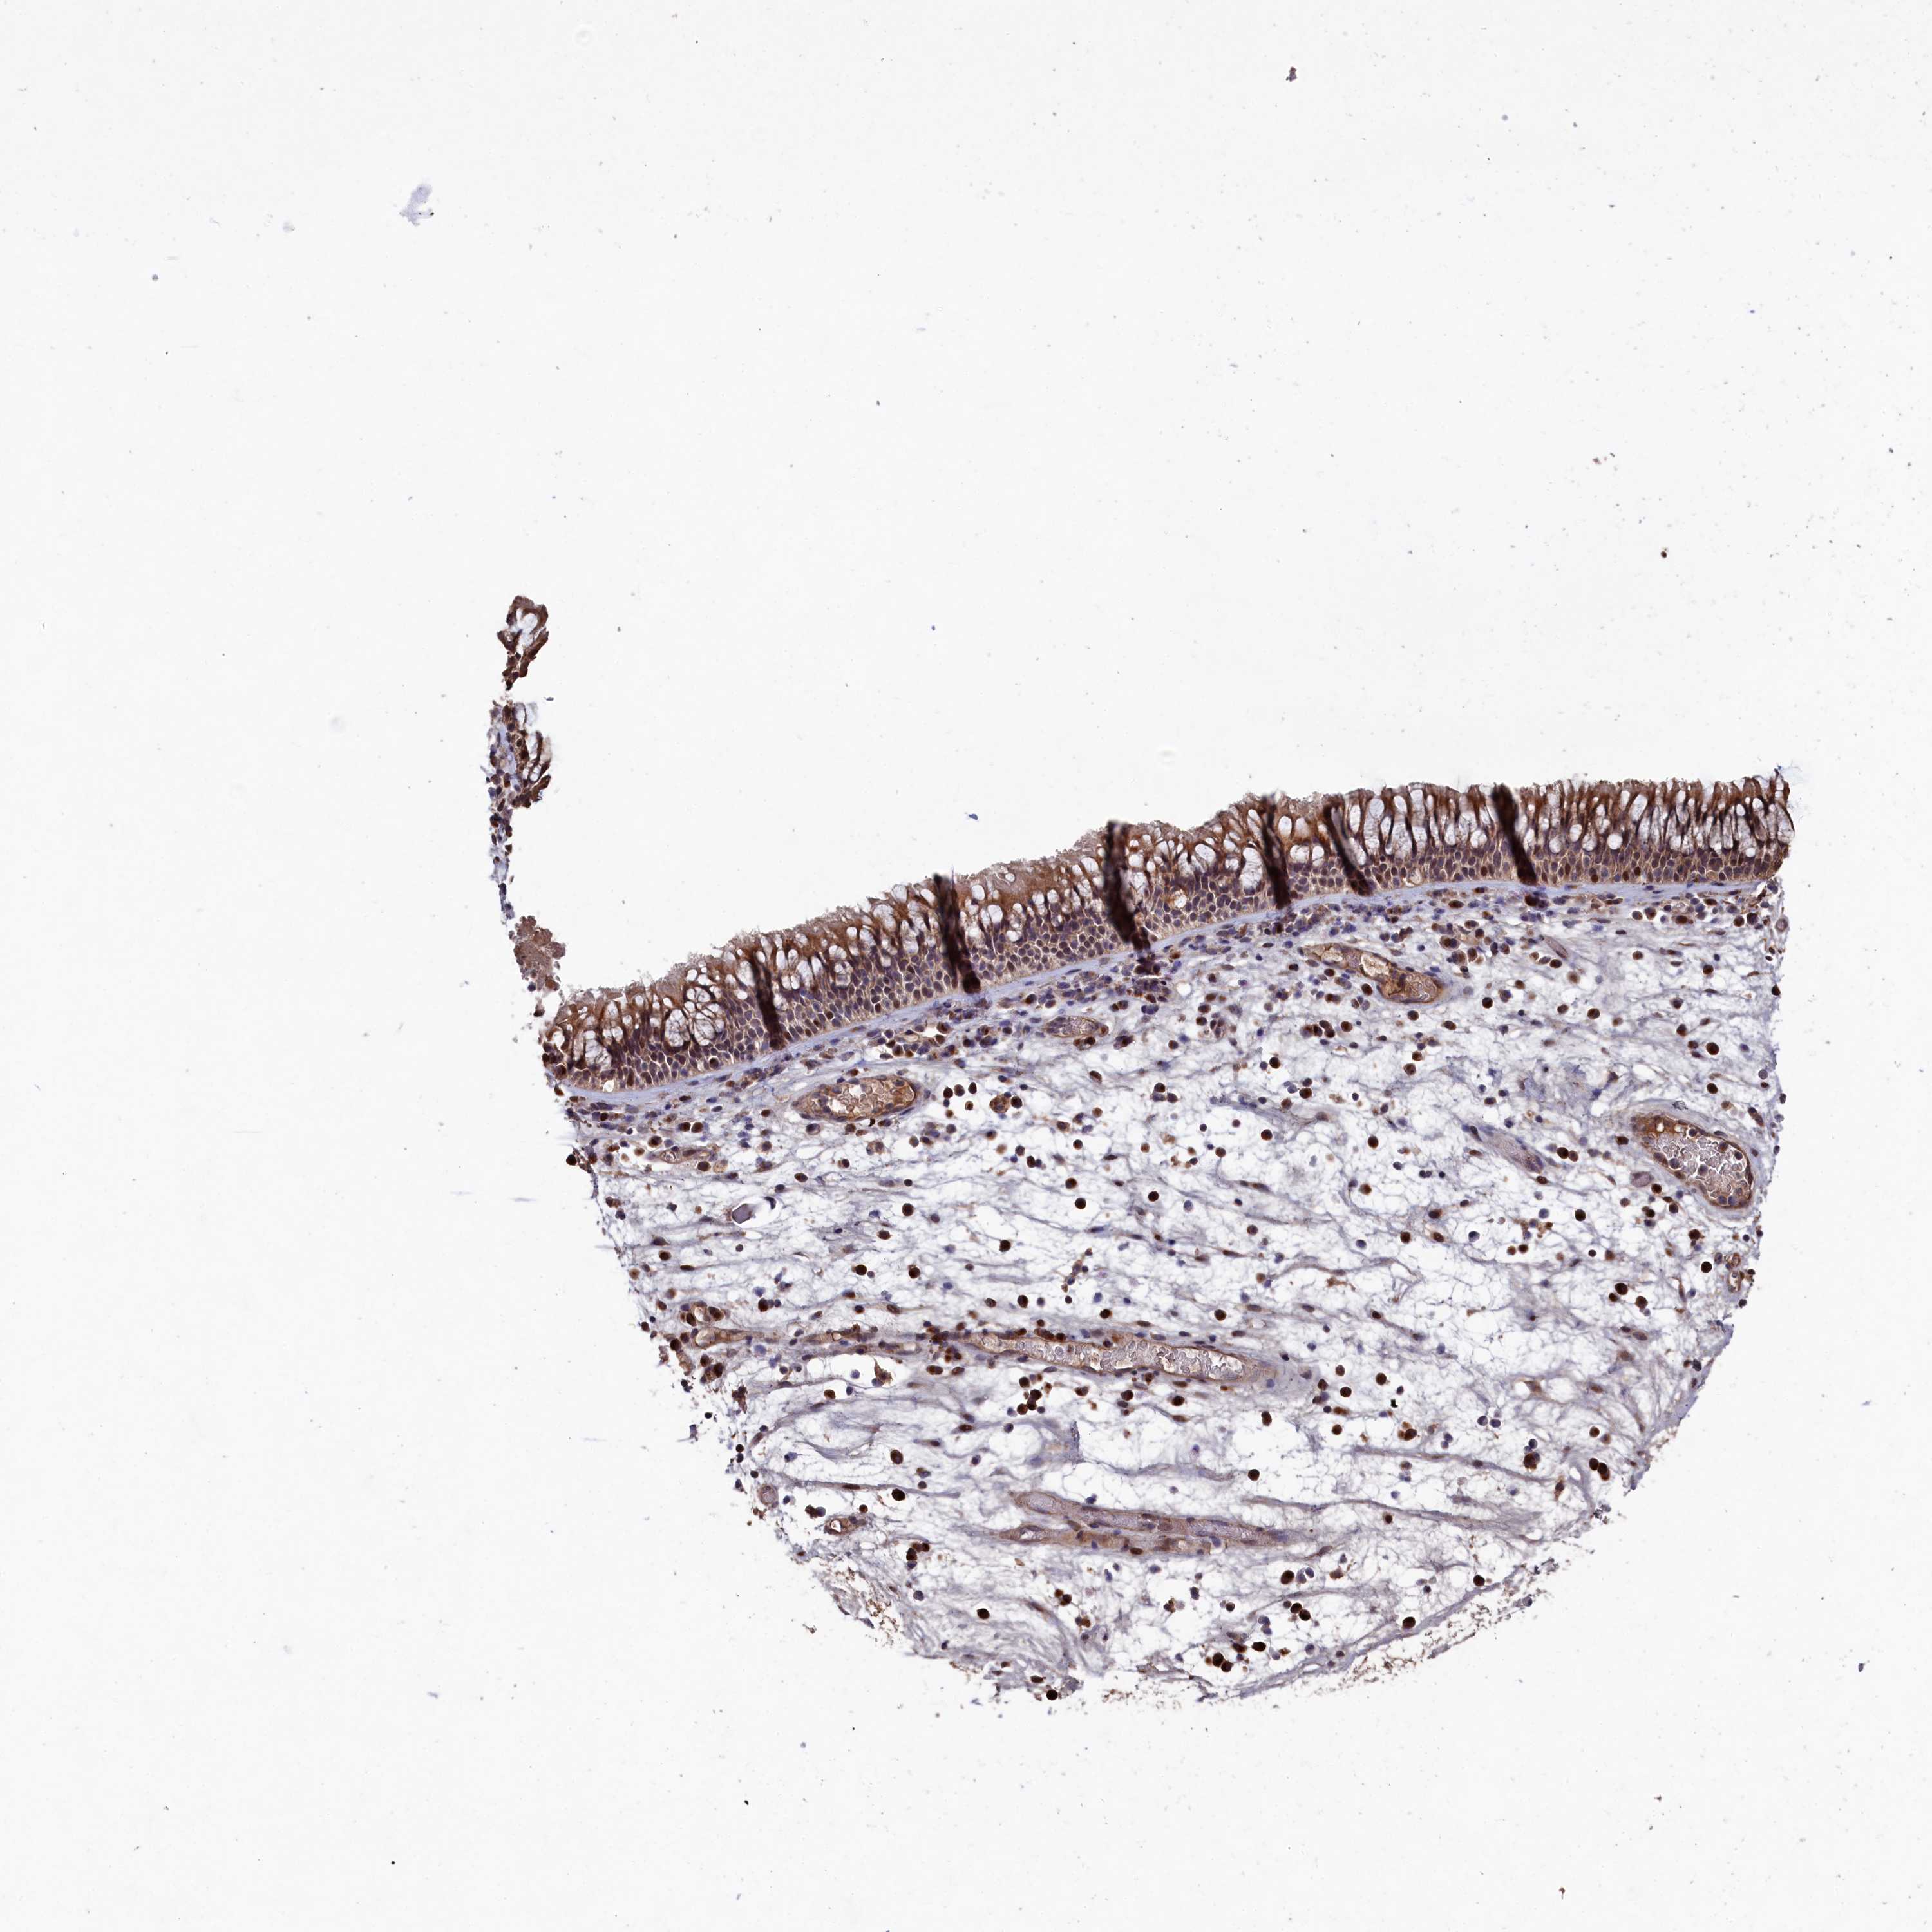

NAA60